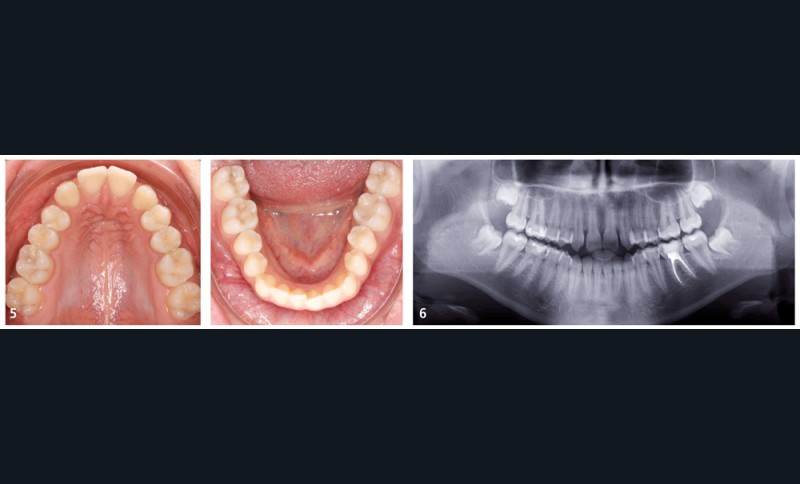

La jeune patiente présente, à l’examen clinique extra-oral, une tendance classe III qui se traduit par une protrusion de la lèvre inférieure de profil, et un menton très présent lors du sourire (fig. 1). À l’examen intra-oral, l’arcade maxillaire est en V, les incisives latérales permanentes droite (12) et gauche (22) sont manquantes et les espaces presque refermés. À l’arcade mandibulaire, un léger encombrement incisif est présent. En occlusion, elle présente une classe I molaire et canine et une occlusion inversée antérieure qui se prolonge à droite sur la première prémolaire (14) (fig. 2 à 5).

La radiographie panoramique (fig. 6) confirme le diagnostic d’agénésies des incisives latérales maxillaires et indique la présence de lésions carieuses proximales sur les molaires mandibulaires, à soigner avant de débuter le traitement.